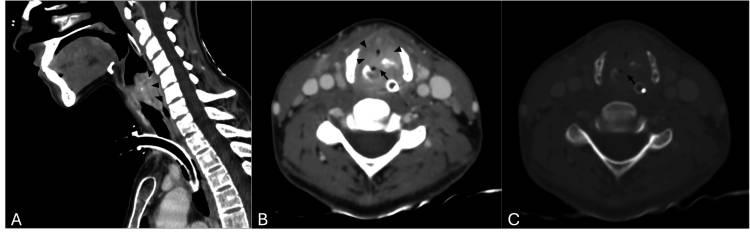

进行了新的CT扫描,结果显示环状软骨完全轴向骨折,偏斜6mm,马蹄形声门下脓肿导致气道明显狭窄(图1)。

图1 (A) 矢状位和(B,C)轴位计算机断层扫描图像显示环状软骨移位、垂直向的完全骨折(箭头),伴有声门下脓肿(箭头)